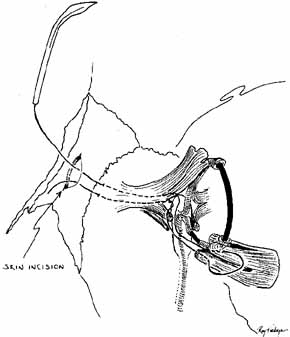

is aided by irrigation with 0.5 mL of an antibiotic steroid solution.  Fig. 19 Probing and irrigation of the nasolacrimal system. Hydraulic pressure is

used in an attempt to force fluid through the obstruction at the valve

of Hasner. If this attempt is unsuccessful, the cannula is slipped

down to the point of obstruction and pushed through gently but firmly. Dye

is injected from the syringe, and the patency of the system is confirmed

by suctioning the dye from the inferior meatus with a soft pediatric-size

plastic suction catheter. Fig. 19 Probing and irrigation of the nasolacrimal system. Hydraulic pressure is

used in an attempt to force fluid through the obstruction at the valve

of Hasner. If this attempt is unsuccessful, the cannula is slipped

down to the point of obstruction and pushed through gently but firmly. Dye

is injected from the syringe, and the patency of the system is confirmed

by suctioning the dye from the inferior meatus with a soft pediatric-size

plastic suction catheter.